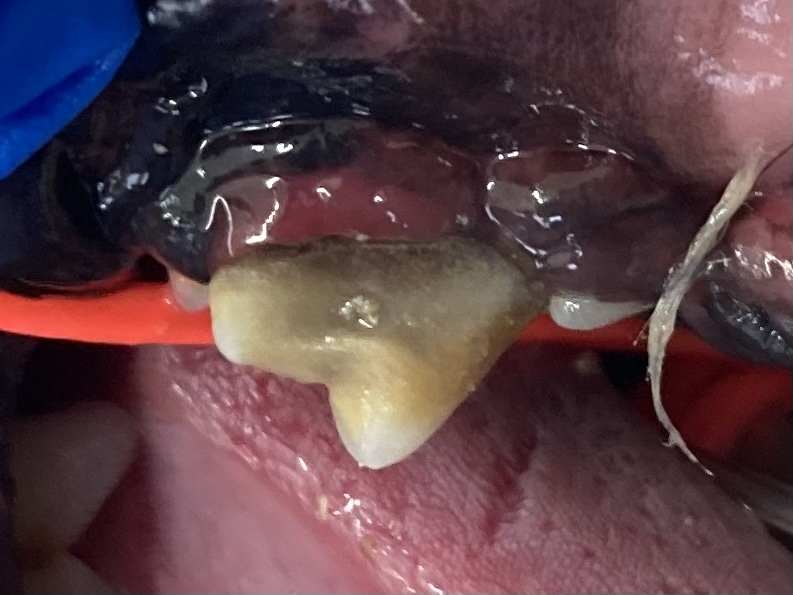

今回は、犬や猫でよく見られる口腔疾患 「歯根膿瘍(しこんのうよう)」 についてご紹介します。

歯根膿瘍とは、歯の根の周囲に膿がたまる病気です。

歯髄や歯周組織に細菌が侵入し、炎症が進行して化膿します。放置すると、骨や周囲組織にまで感染が広がる危険があります。

- 歯の破折(はせつ):露髄から細菌が侵入